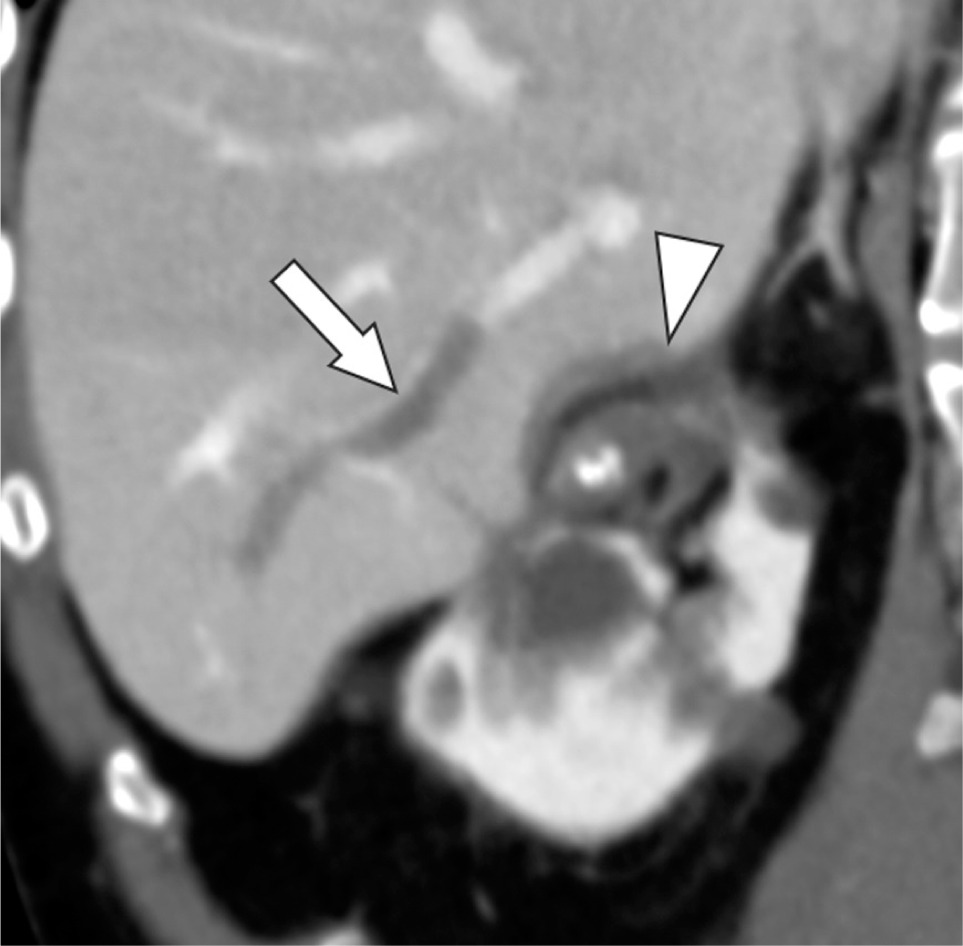

Figure 1: Oblique coronal contrast-enhanced CT before cryoablation reveals the normal liver parenchyma and patent portal vein branch (arrow).

Figure 2: Oblique coronal contrast-enhanced CT 2 days after cryoablation reveals the ablated liver parenchyma (arrowhead) and portal venous thrombus (arrow).